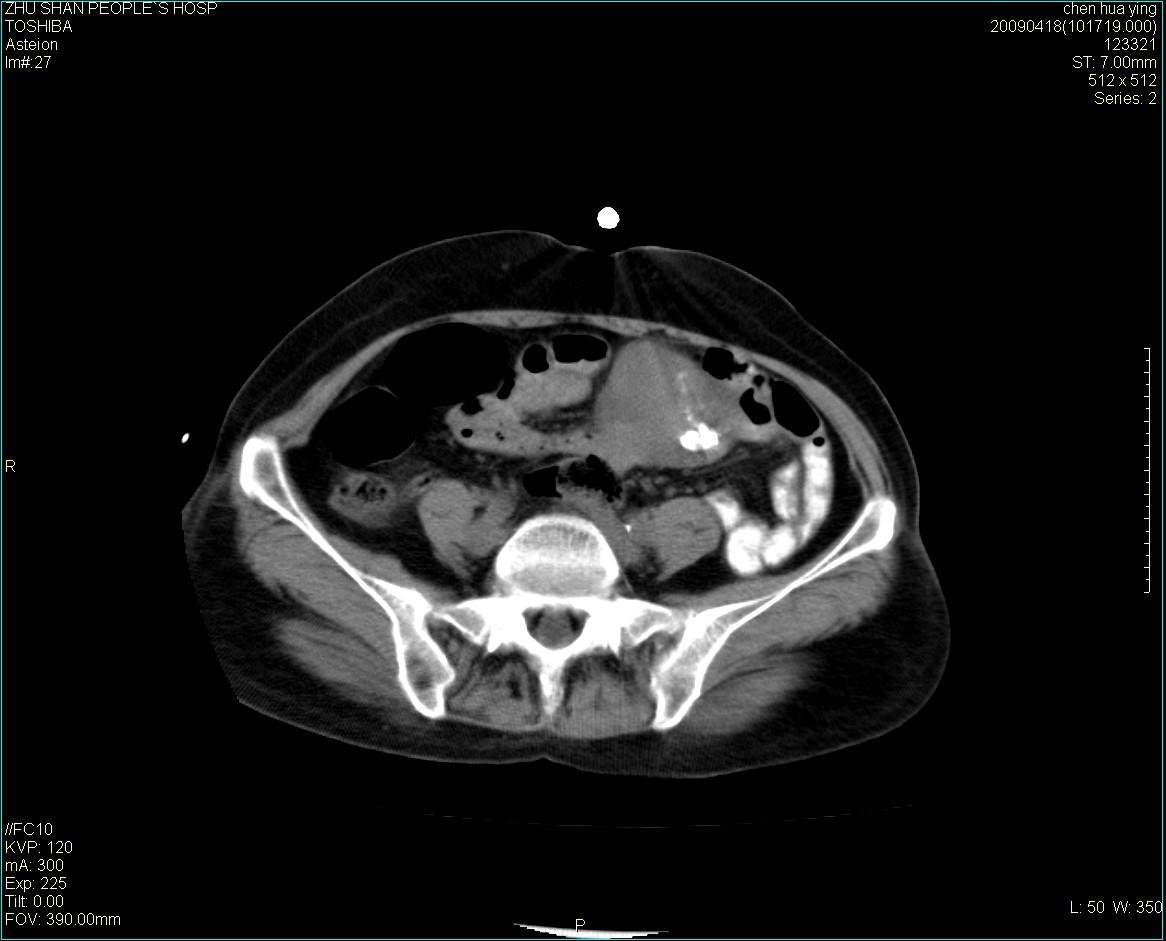

女性病人 65岁 腹部包块半年余结肠造影未见异常.

病灶略呈圆形有分叶状,上部层面呈实性,右侧见圆形低密度区,灶内见团块状钙化,病灶下方与肠管分境不清,考虑间质瘤可能性大,建议肠道准备后增强